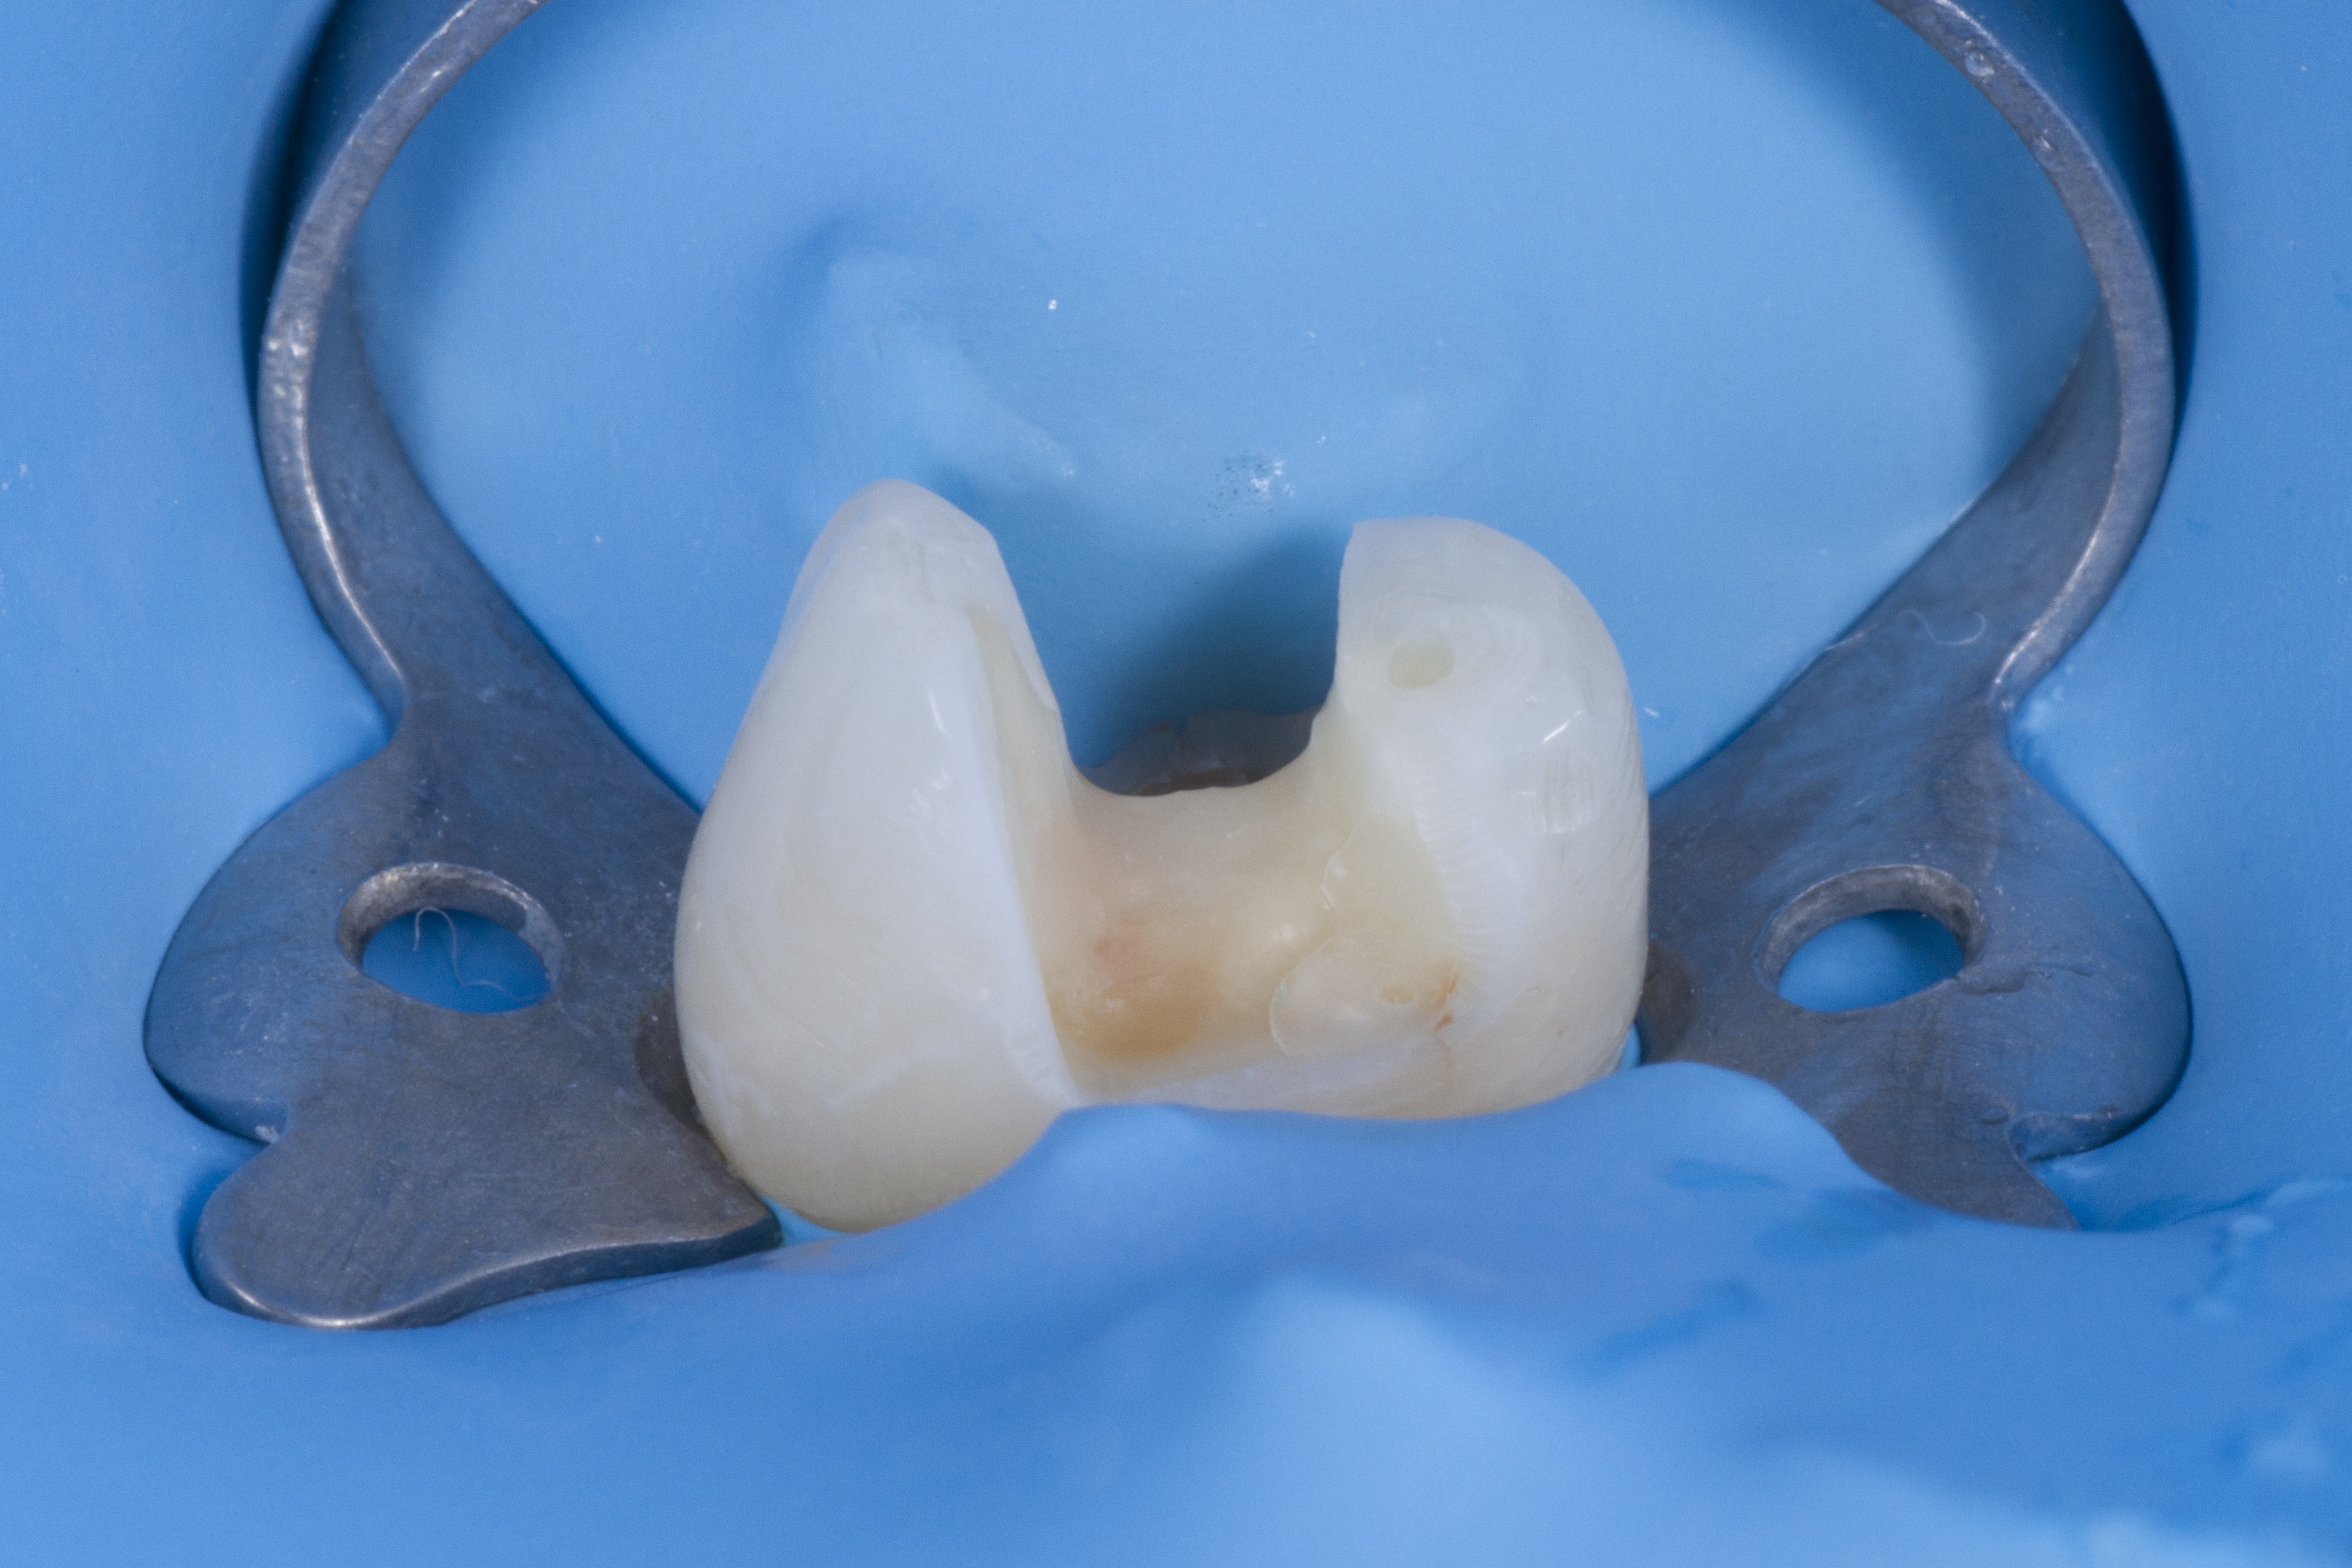

L’érosion-infiltration

Cette technique permet de faire disparaitre les taches blanches (et parfois brunes) sur les dents. Pour les plus superficielles d’entre elles, aucune instrumentation n’est nécessaire.

Avant-après :